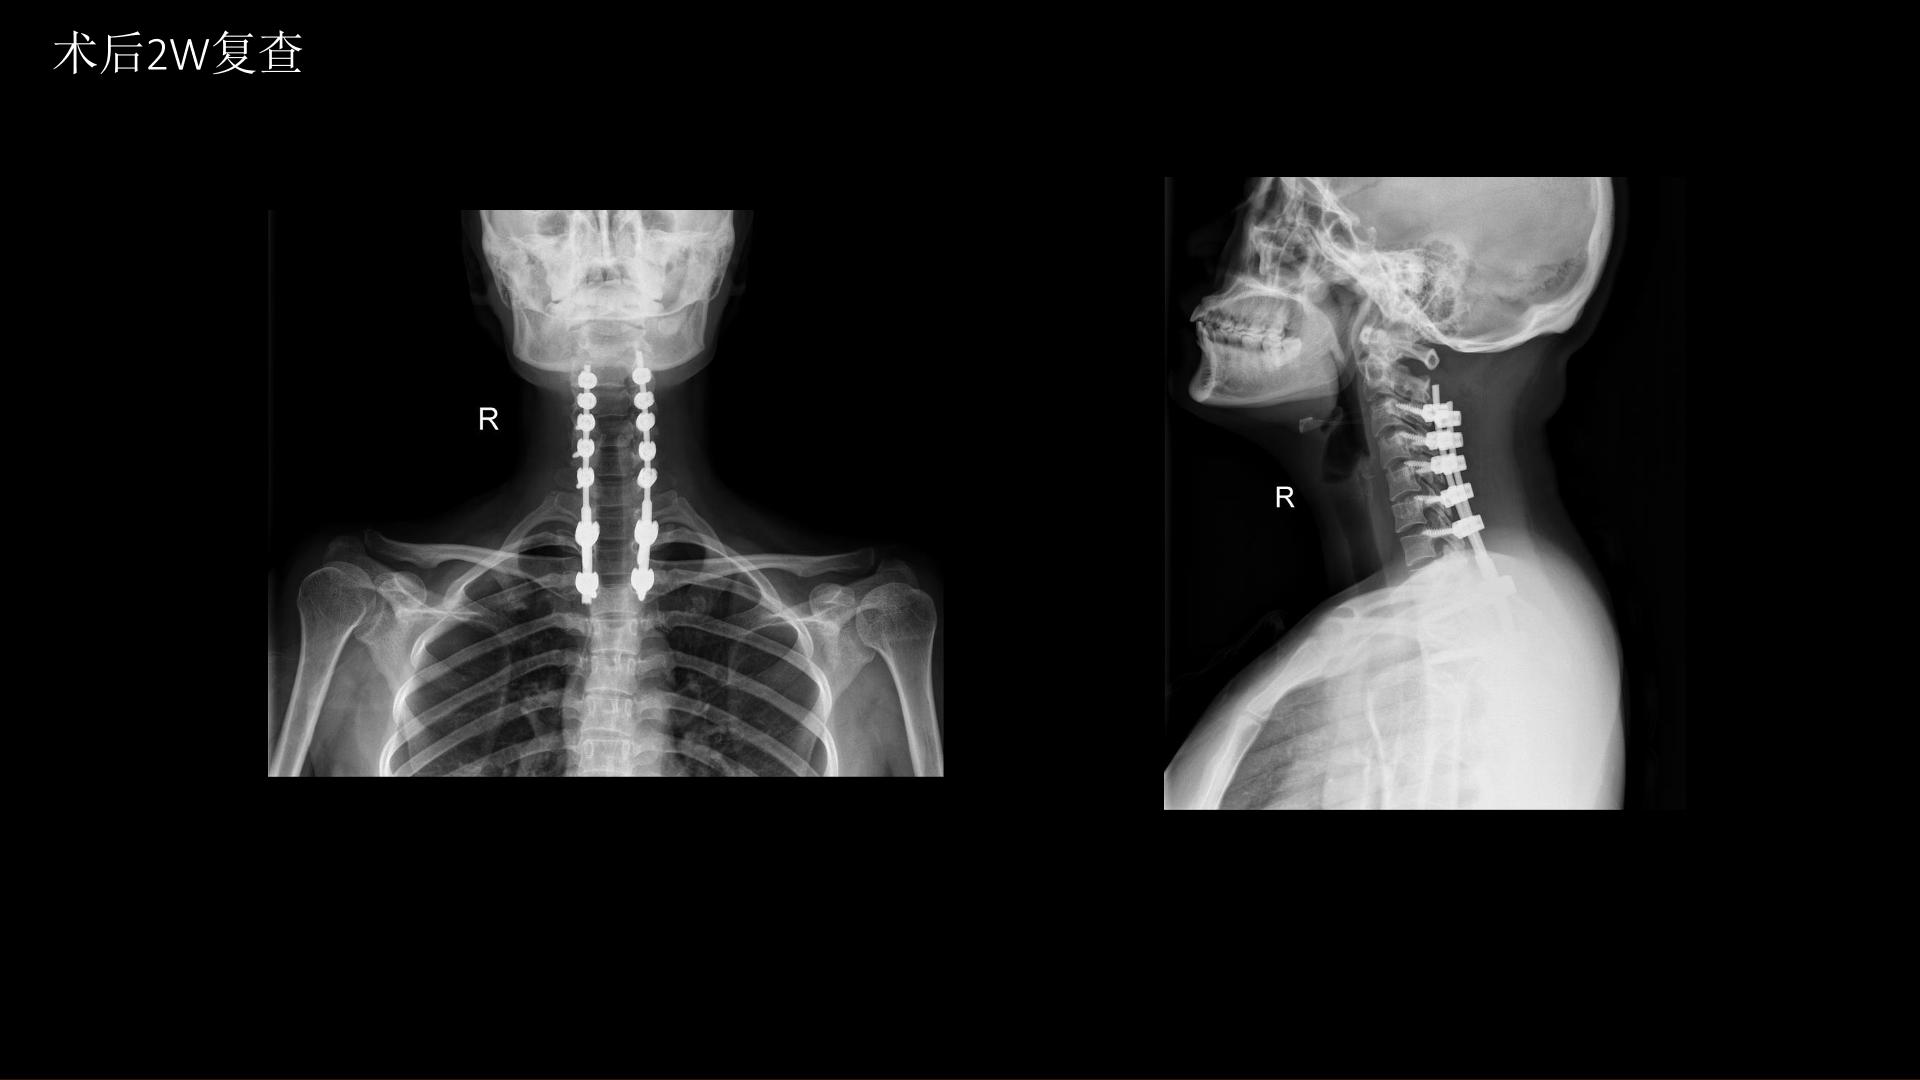

西安交通大学第二附属医院刘重霄教授团队:一例巨长型颈胸椎神经鞘瘤切除术+脊柱内固定术